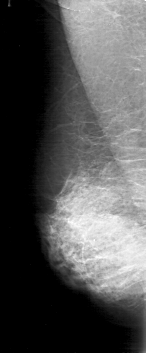

D_4158_1.RIGHT_CC

RIGHT_CC LINES 4981 PIXELS_PER_LINE 2281 BITS_PER_PIXEL 12 RESOLUTION 43.5 NON_OVERLAY